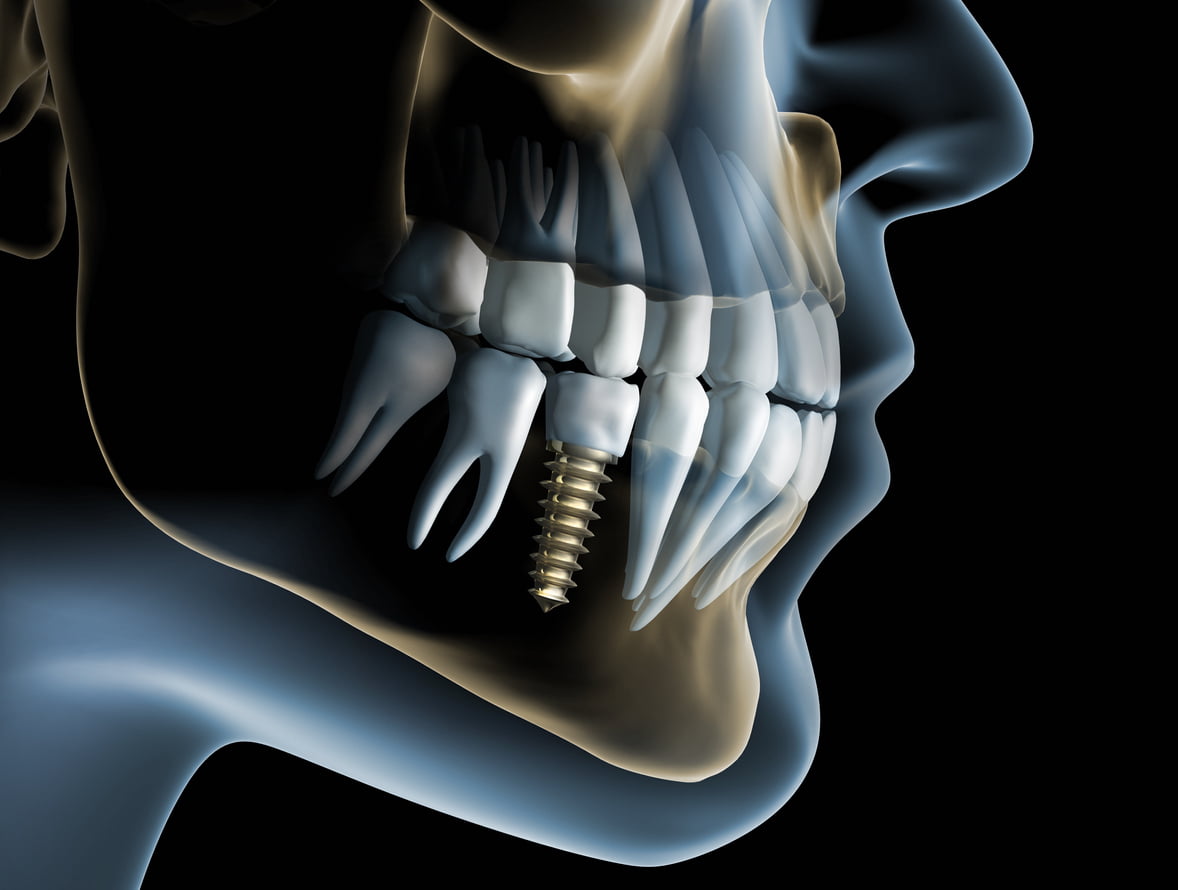

Titanium implants are inserted into your jaw to create a fixed new tooth root. As titanium is very well tolerated by the body, over time the implant post fuses to the surrounding jawbone, becoming a solid and secure foundation for a crown or bridge. There is never a worry that the restoration will slip or fail, and the benefits to your quality of life are huge. Replacing your missing teeth with implants has a significant improvement on the way you eat, speak and feel, as well as supporting your facial structure and remaining teeth.

The titanium implant is placed into your jawbone during an in-surgery appointment. We use local anaesthetic to minimise any discomfort, and ensure you feel relaxed before we begin. Once fitted, the implant will take 3-6 months to heal and bond with your bone, so we place a temporary tooth to protect your gum as your implants heals.

In some cases, often if a tooth has been missing for a significant amount of time, or the condition of the teeth has deteriorated, there can be a loss of bone in the jaw as a result. This would prevent the successful placement of a dental implant, which needs to fuse to the natural jawbone to provide a solid foundation. With a bone graft, we can help return this stability and add enough bone density for implant placement.